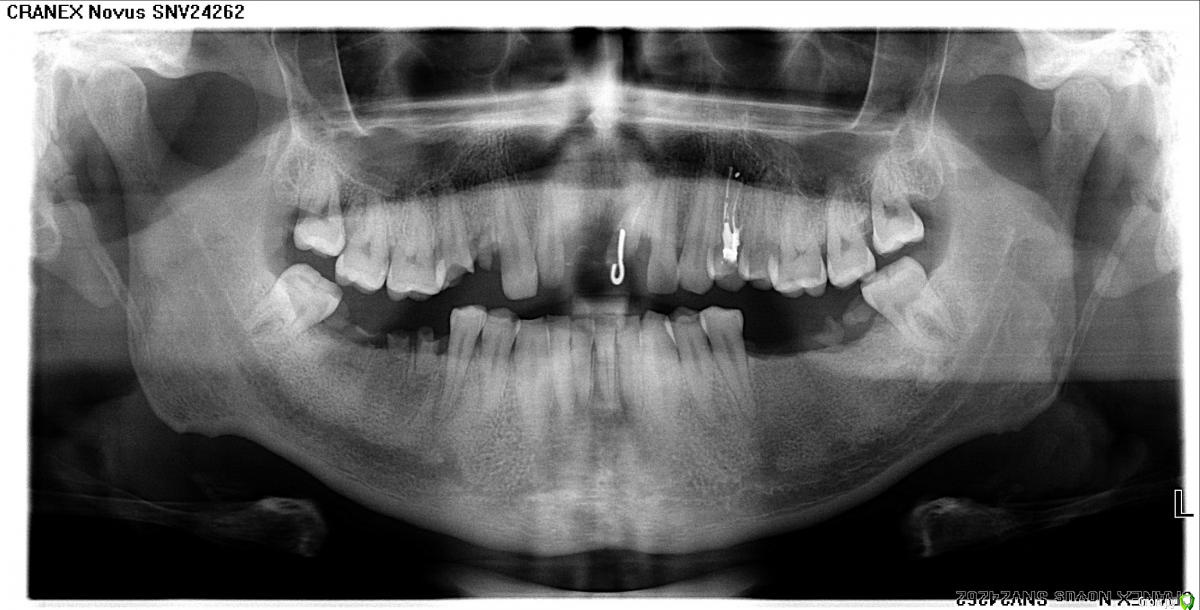

Владимир Андреевич Опубликовано 6 декабря, 2019 Поделиться Опубликовано 6 декабря, 2019 Здравствуйте! Помогите, пожалуйста, советом.Ситуация такая - нет нижних жевательных с обоих сторон...нет уже давно, верхние зубы выдвинулись в сторонуотсутствующих. Сейчас есть возможность заняться зубами, поставить импланты, но под них банально нет места(С одной стороны всё более-менее, место нашли, а вот с другой стороны совсем беда, причем там еще и сверху одного зубанет (и один сильно стерся, но он еще пригоден для протезирования), соответственно нижние выдвинулись в сторону верхних, отсутствующих.Ортопед говорит, что ортодонтия тут не поможет (вот вообще никак!), предложил ставить огромную дугу, с 6ки до 6ки, но мне такой план совсем не по нраву...Помогите, пожалуйста! Можно ли что-то сделать в таком случае, чтобы хоть немного места освободить (потом, возможно, подпилить те зубы, которые мешают)?34 года Ссылка на комментарий

Владимир Андреевич Опубликовано 6 декабря, 2019 Автор Поделиться Опубликовано 6 декабря, 2019 Покажите панорамный снимокЯ недавно 3D делал, а панорамный года 3 назад, не знаю, актуально ли... Ссылка на комментарий